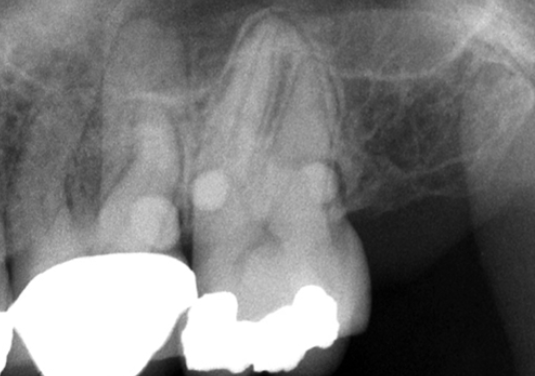

<p>4. Using Fig. 5.24, what would you call the enamel projections seen on the maxillary molars?</p><p>a. Enamel pearl</p><p>b. Enamel projection</p><p>c. Hypercementosis</p><p>d. Dens in dente</p>

4. Using Fig. 5.24, what would you call the enamel projections seen on the maxillary molars?

a. Enamel pearl

33. Where is a cervical enamel projection normally found?

a. Near any furcation